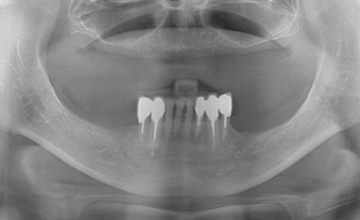

몇 개의 임플란트를 심은 뒤, 완성된 임플란트에 부분 틀니를 연결해 흔들림 없이 안정감 있게 사용할 수 있으며 스스로 탈착은 불가능합니다.

적은 수의 임플란트를 심으면서도 입안의 틀니가 움직이지 않도록 고정해 주어 식사하는 데 부담이 적습니다.